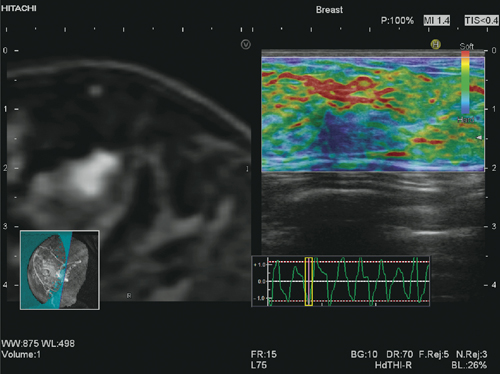

■Real-time Virtual Sonography(RVS)との併用

“Real-time Virtual Sonography(RVS)”は,超音波画像と同一断面のCT/MR/USのスライス断面をリアルタイムに並列表示する機能である(図4)。プローブに取り付けた位置センサの情報を用い,あらかじめ取得したボリュームデータから,超音波画像と同一断面のmulti-planar reconstruction(MPR)画像をリアルタイムに再構成する。

RVSと併用することで,Elastographyの可能性がさらに広がるものと期待されている。

図4 乳腺MR-RVS+Real-time Tissue Elastography